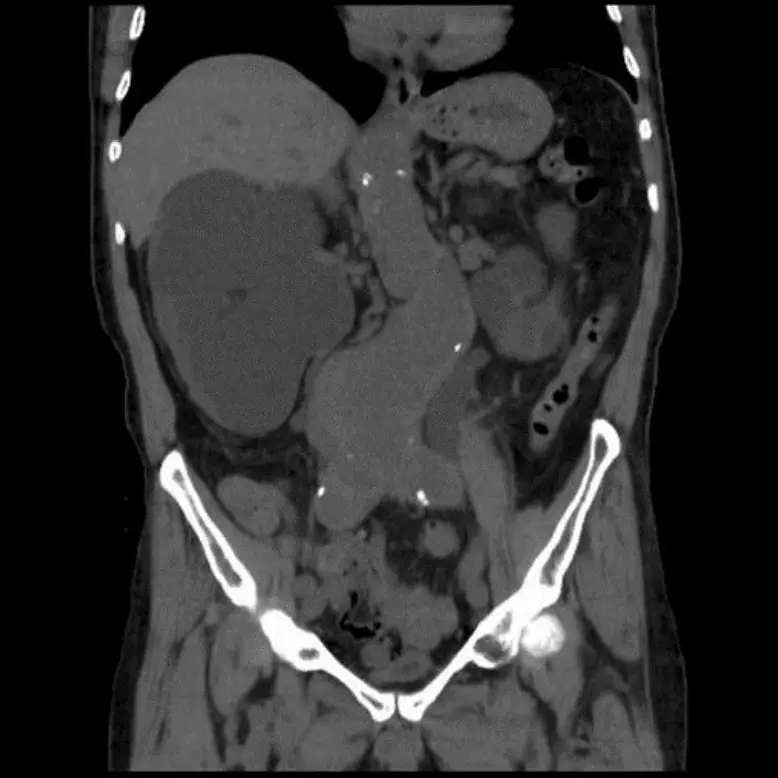

一位64歲男性病人有高血壓病史,現腎功能變差,腎臟超音波顯示有腎水腫(hydronephrosis)現象,腹部及骨盆腔電腦斷層顯示如圖,下列何者是最可能的病因?

從腹部骨盆腔電腦斷層(CT)冠狀面影像可見:

- 腹主動脈遠端(infrarenal region)呈顯著擴張,直徑明顯大於正常,符合動脈瘤(AAA)特徵。

- 動脈瘤周邊可見一層均質軟組織密度的「mantle」(軟組織緣),即主動脈壁增厚並伴隨周邊纖維化性炎症反應,常見於IAAA (radiologykey.com)。

- 軟組織緣向外延伸,纏繞並向內擠壓雙側輸尿管(輸尿管走行於動脈旁),造成輸尿管中段迂曲、受壓及近端積水。

這些影像特徵與單純動脈粥樣硬化性AAA不同,後者周邊少有高密度炎性肉芽或纖維組織緣;也非多囊腎表現,因腎臟本身並未見多發高密度囊腫。